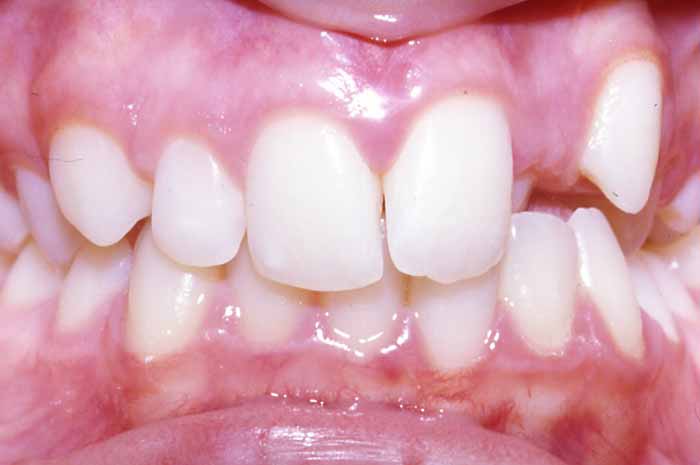

Mordida cruzada anterior

Uno o varios incisivos superiores se situan por detrás de los inferiores, pudiendo alterar el correcto cierre de la boca.

Ortodoncia convencional con brackets metálicos

En este caso, para conseguir un resultado óptimo, también se utilizó un aparato removible (de quita y pon) en la arcada superior, previo a la colocación del aparato fijo (brackets).

La excepcional colaboración de la paciente fue fundamental para la consecución de los resultados.

Antes y Después